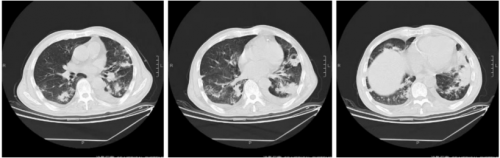

11月3日复查肺ct:炎症局部略有吸收,空洞变化不大。

11.3 肺ct

患者精神状态明显好转,正常进食。可下床活动。